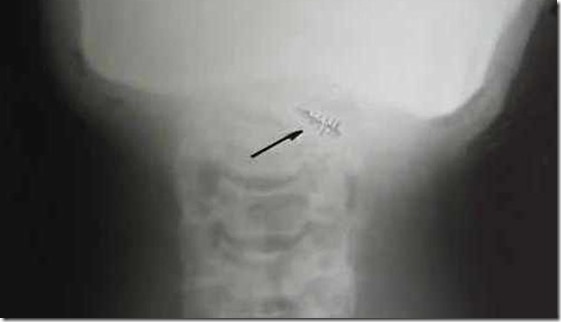

No entanto, tais dispositivos têm sido detectados através de métodos convencionais, tais como raios X e ultra-sonografia. Existem ainda relatos de pessoas que ficaram extremamente doentes após a remoção cirúrgica dos implantes alienígenas.